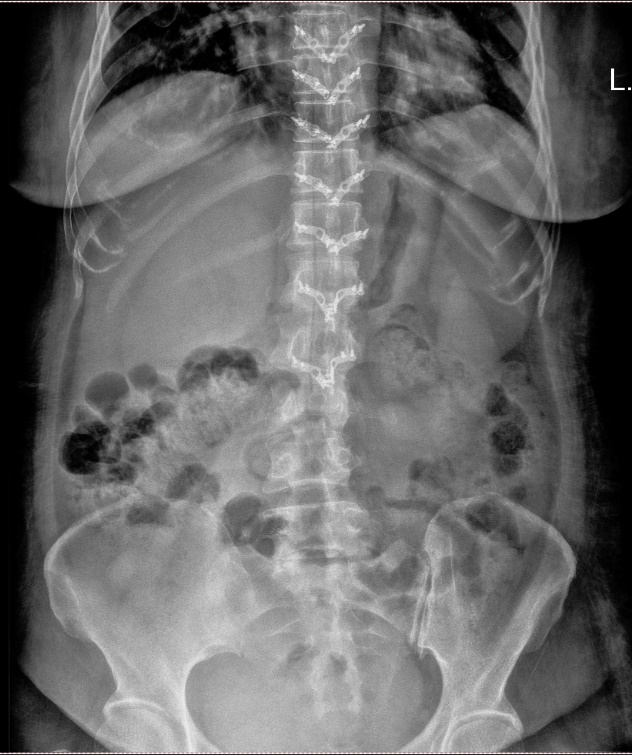

病例3:女性,31岁

患者以“腰部疼痛半月,加重3天”为主诉入院,自诉腰部疼痛,休息后无缓解。专科查体:腰部压痛及叩击痛+,双下肢小腿肌群肌力Ⅳ级+,感觉正常,无明显病理征。

结合患者影像学资料,女性,髓外硬膜下病变,病变位于胸腰段,节段较长,位于圆锥附近,T1、T2混杂信号,并合并有脂肪信号,患者症状较轻,病情发展时间较长,倾向于畸胎瘤可能。

行“胸腰椎椎管内肿瘤切除+钉棒内固定术”,术后腰部疼痛症状明显缓解,下肢肌力恢复正常。